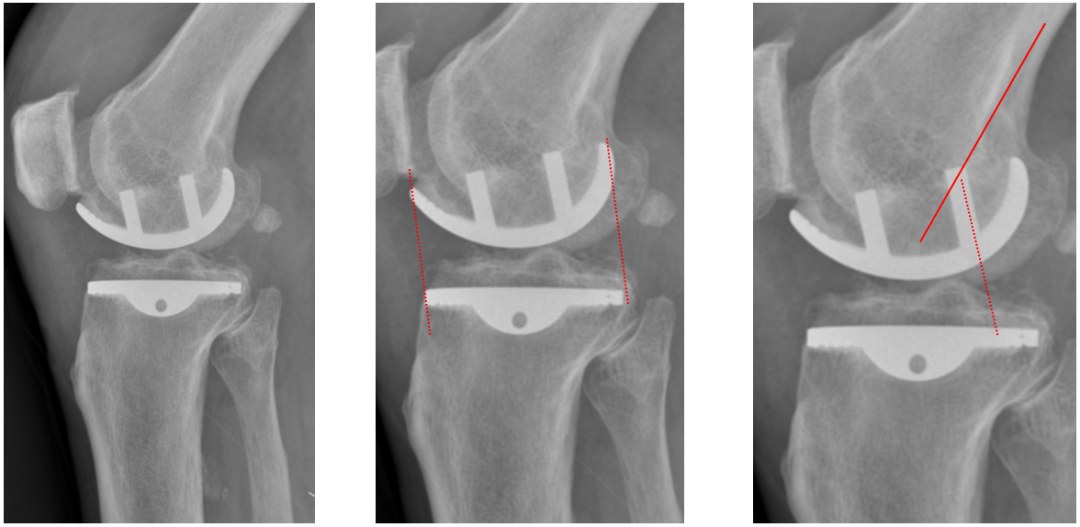

侧位片标准胫骨和股骨假体位置

侧位片假体位置:股骨假体长栓与短栓平行,后倾35°;假体后缘与股骨后髁齐平,胫骨假体后倾7°,与胫骨平台前后缘齐平。

胫骨假体厚度合适

胫骨垫片厚度合适:术前内翻畸形基本矫正,残留2-3°内翻。

胫骨假体偏大,且后倾不足

侧位胫骨假体位置:胫骨假体后侧悬挂>2mm,后倾2°。

胫骨假体后倾角度大

侧位片胫骨假体位置:胫骨假体后倾12°,前后缘齐平 。

股骨假体偏小

侧位片股骨假体位置:股骨假体偏小,与胫骨假体后缘不齐平;屈曲15°,未包容股骨后髁。

股骨假体偏大

侧位片股骨假体位置:股骨假体与胫骨假体不匹配,股骨假体大一个型号,屈曲45°,后缘空虚。

股骨假体屈曲角度大

侧位片股骨假体位置:股骨假体与胫骨假体匹配,股骨假体屈曲62°,前缘翘起。